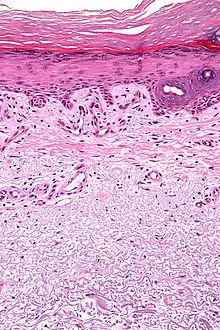

Micrograph showing solar elastosis - grey, jumbled spaghetti-like material on bottom of image. H&E stain. | |

In the earlier stages of actinic elastosis, elastic fiber proliferation can be seen in the dermis. As the condition becomes more established, the collagen fibers of the papillary dermis and reticular dermis become increasingly replaced by thickened and curled fibers that form tangled masses and appear basophilic under routine haematoxylin and eosin staining. These fibers stain black with the Verhoeff stain.[2]